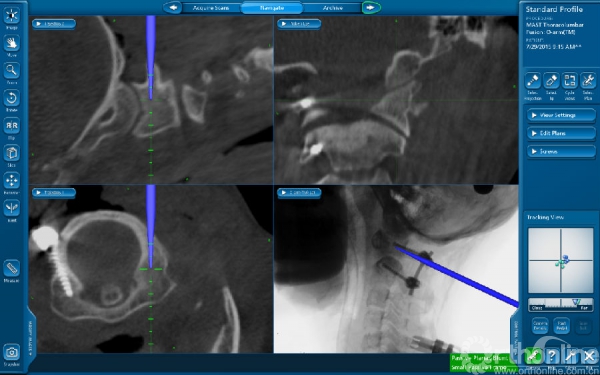

患者杨静(化名)15岁,发现颈椎先天性畸形10余年,持续的多年支具外固定,活动后颈部疼痛,严重影响生活,后慕名到西京骨科医院就诊。入院后由桑宏勋副主任为其进行了全面病情评估,发现患者寰枢椎畸形严重,并伴有椎动脉高跨,病情复杂手术风险大,经过科室讨论决定为其实施“导航辅助下寰枢椎脱位复位、椎弓根螺钉内固定、植骨融合术”。术中利用O-arm扫描获得患者实时影像数据,导入导航系统进行三维重建后进行精准的置钉、复位等手术操作。相对于传统手术方式,O-arm联合导航系统可以使手术操作可视化、精准化,减少手术时间与术中出血量,降低患者手术风险。术后患者恢复良好并已康复出院。

术中影像图片